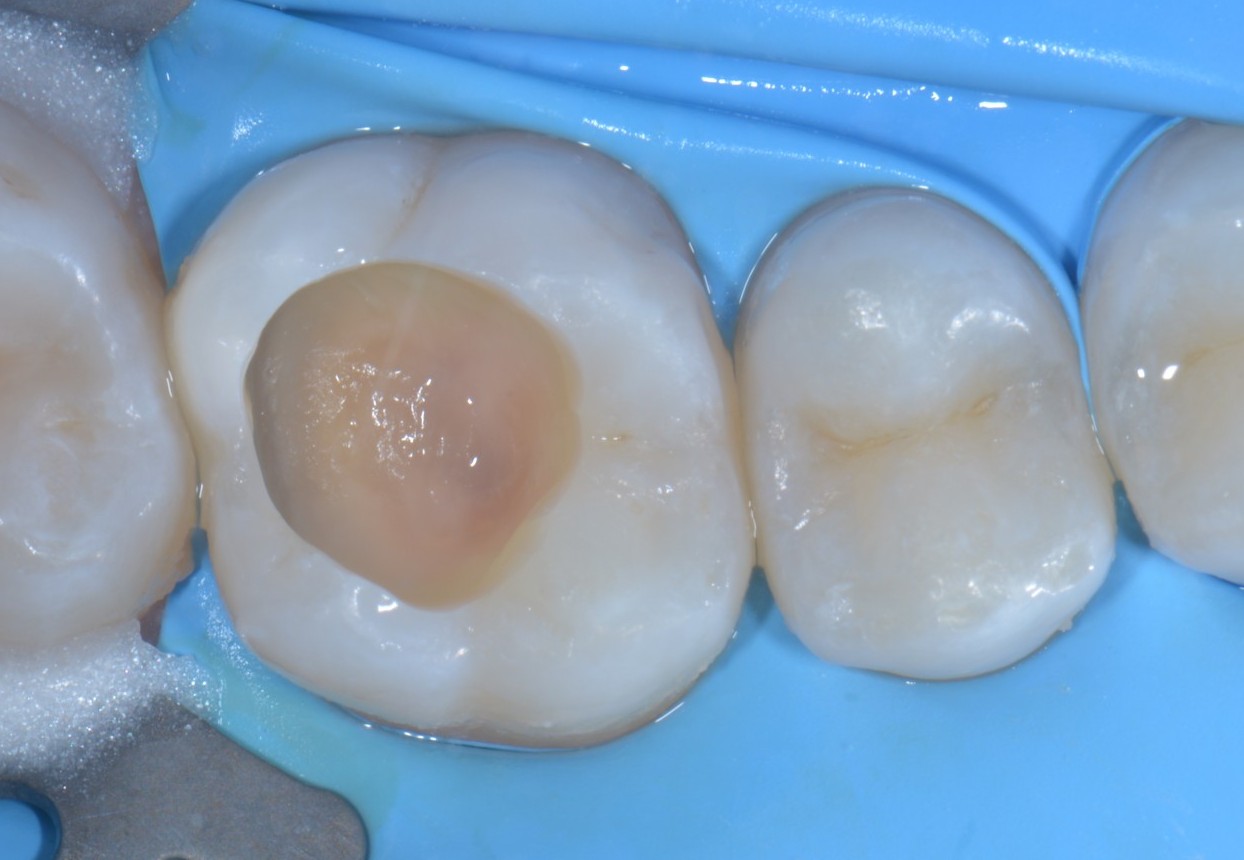

In primis quella che utilizzo di più e forse la più banale, ovvero, l’isolamento dei denti adiacenti in corso di cementazione di corone, faccette o intarsi.

A partire dalle fasi di mordenzatura o sabbiatura il teflon protegge i denti adiacenti senza creare spessori, resta aderente alle superfici, può essere invaginato sotto gengiva. Quando arriva il momento di rimuoverlo scivola via semplicemente ed è pure bello per la documentazione fotografica, soprattutto per l’effetto che fa quando ci lasci qualche goccia d’acqua…

Un altro bellissimo utilizzo per il teflon è lo stampaggio del piano occlusale nelle otturazioni di prima classe (o se ti ingegni anche per le seconde classi) quando il dente da trattare conserva ancora la sua anatomia originale. In questi casi puoi utilizzare del sigillante dei solchi unitamente a del composito flow per creare lo stampo della superficie occlusale, poi, quando arrivi all’ultima applicazione di composito, lo distribuisci a riempimento della superficie occlusale, ci apponi sopra del teflon, premi lo stampo che avevi creato prima di iniziare a preparare la cavità e rimuovi il tutto tirando via il teflon. A questo punto si tratta solo di eliminare gli eccessi di composito e ritoccare leggermente i solchi et voilà! Hai riprodotto una bellissima anatomia che non richiederà praticamente alcun ritocco occlusale in pochi secondi!